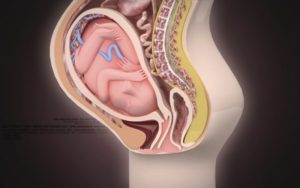

Нормальное положение плодак 39 неделе беременности – продольноес головным предлежанием в тазовуюобласть. Оно считается самым безопаснымдля мамы и малыша.

Когда начнутся роды,такое положение позволит ребенкуспокойно покинуть матку. Если плод лежитножками вниз, наискосок или поперек, тоэто определяется врачами как осложнение.

Высотастояния дна матки на 39 неделе составляетоколо 40 см. Нетрудно догадаться, чтоживот беременной женщины на данномсроке становится очень большим. Малотого, происходит его опускание: ребеноквсе сильнее прижимается к тазовымкостям, вызывая болевые ощущения. Из-заэтого в походке появляется неповоротливостьи неловкость. Становится все тяжелеепринять удобное положение.

Как правило, плод к этому времени располагается головкой вниз. Бывает, что ребенок не переворачивается в нужное положение, а остается лежать ножками вниз (тазовое предлежание). Тогда врач рекомендует роженице выполнять специальный комплекс упражнений, помогающих малышу занять подходящую позицию.